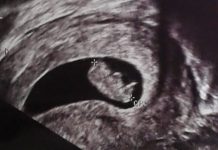

Acupuntura y embarazo

Acupuntura en el embarazo

El embarazo es una etapa muy importante en la vida de una mujer donde se producen muchos cambios, cada uno de los trimestres tiene...